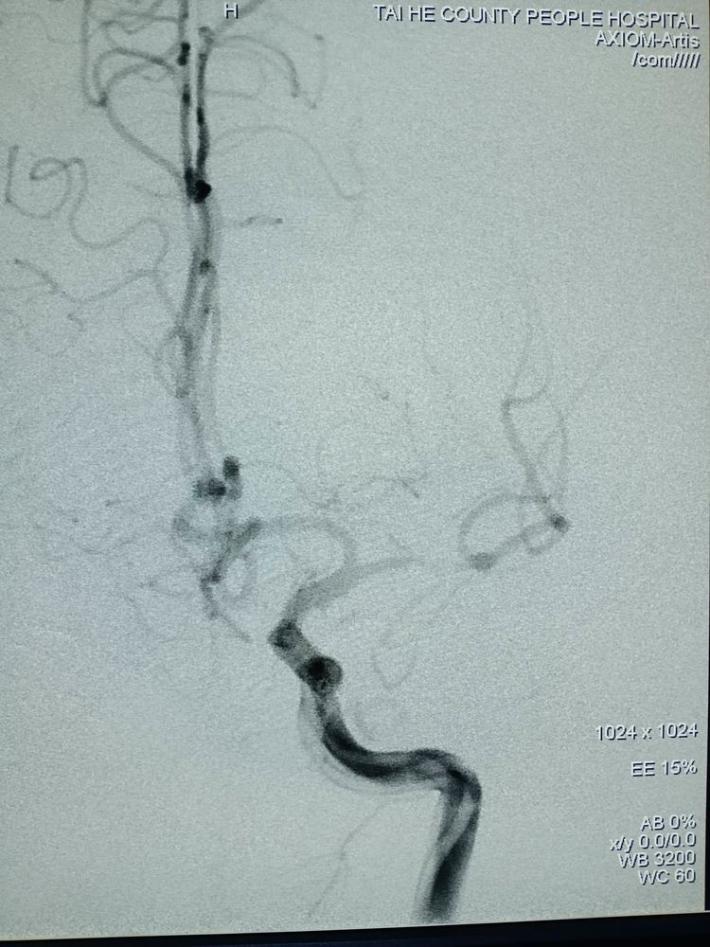

右侧颈总动脉造影提示:右侧颈内动脉颅内段慢性闭塞,非责任病变。

左侧颈总动脉造影提示:左侧大脑中动脉闭塞,考虑责任病变。

左侧椎动脉造影提示:右侧后交通动脉开放,后循环向前循环代偿供血。

微导管超选至闭塞血管的远端,手推造影证实在真腔。

国产取栓支架尼科4mm*20mm成功打开,前向血流恢复。

取栓后五分钟,血流减慢,难以维持,左侧大脑中动脉M1段原位狭窄。